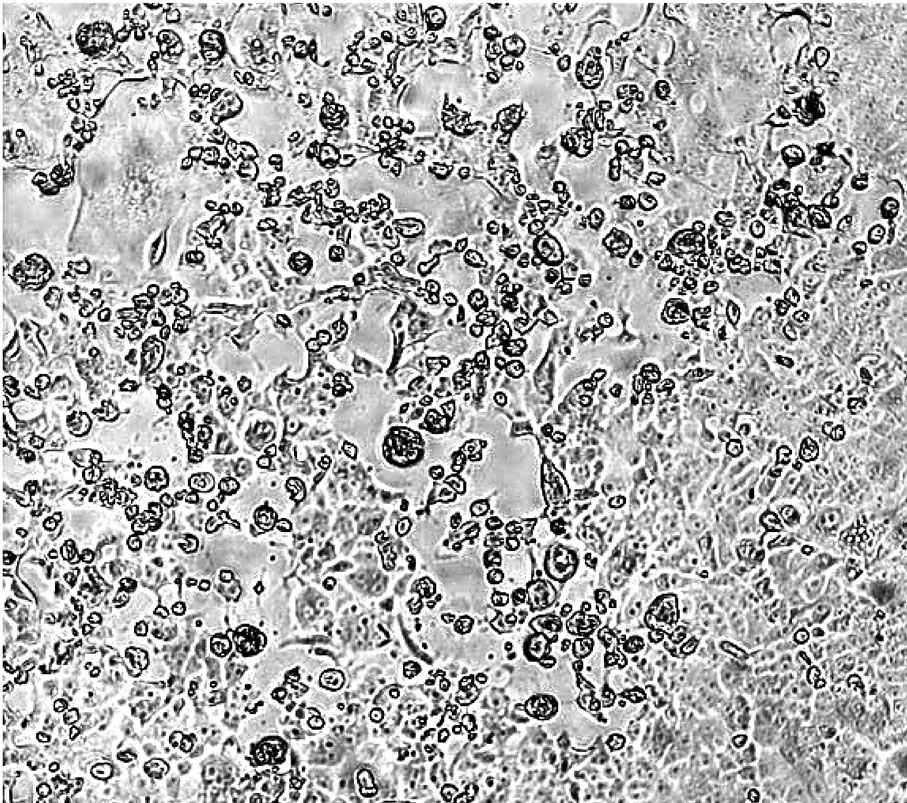

● Omicron變種病毒在混合了科興疫苗接種者的血清之後依然有毒性,有很明顯的細胞病變作用(CPE),細胞大量死亡。 港大微生物學系團隊供圖